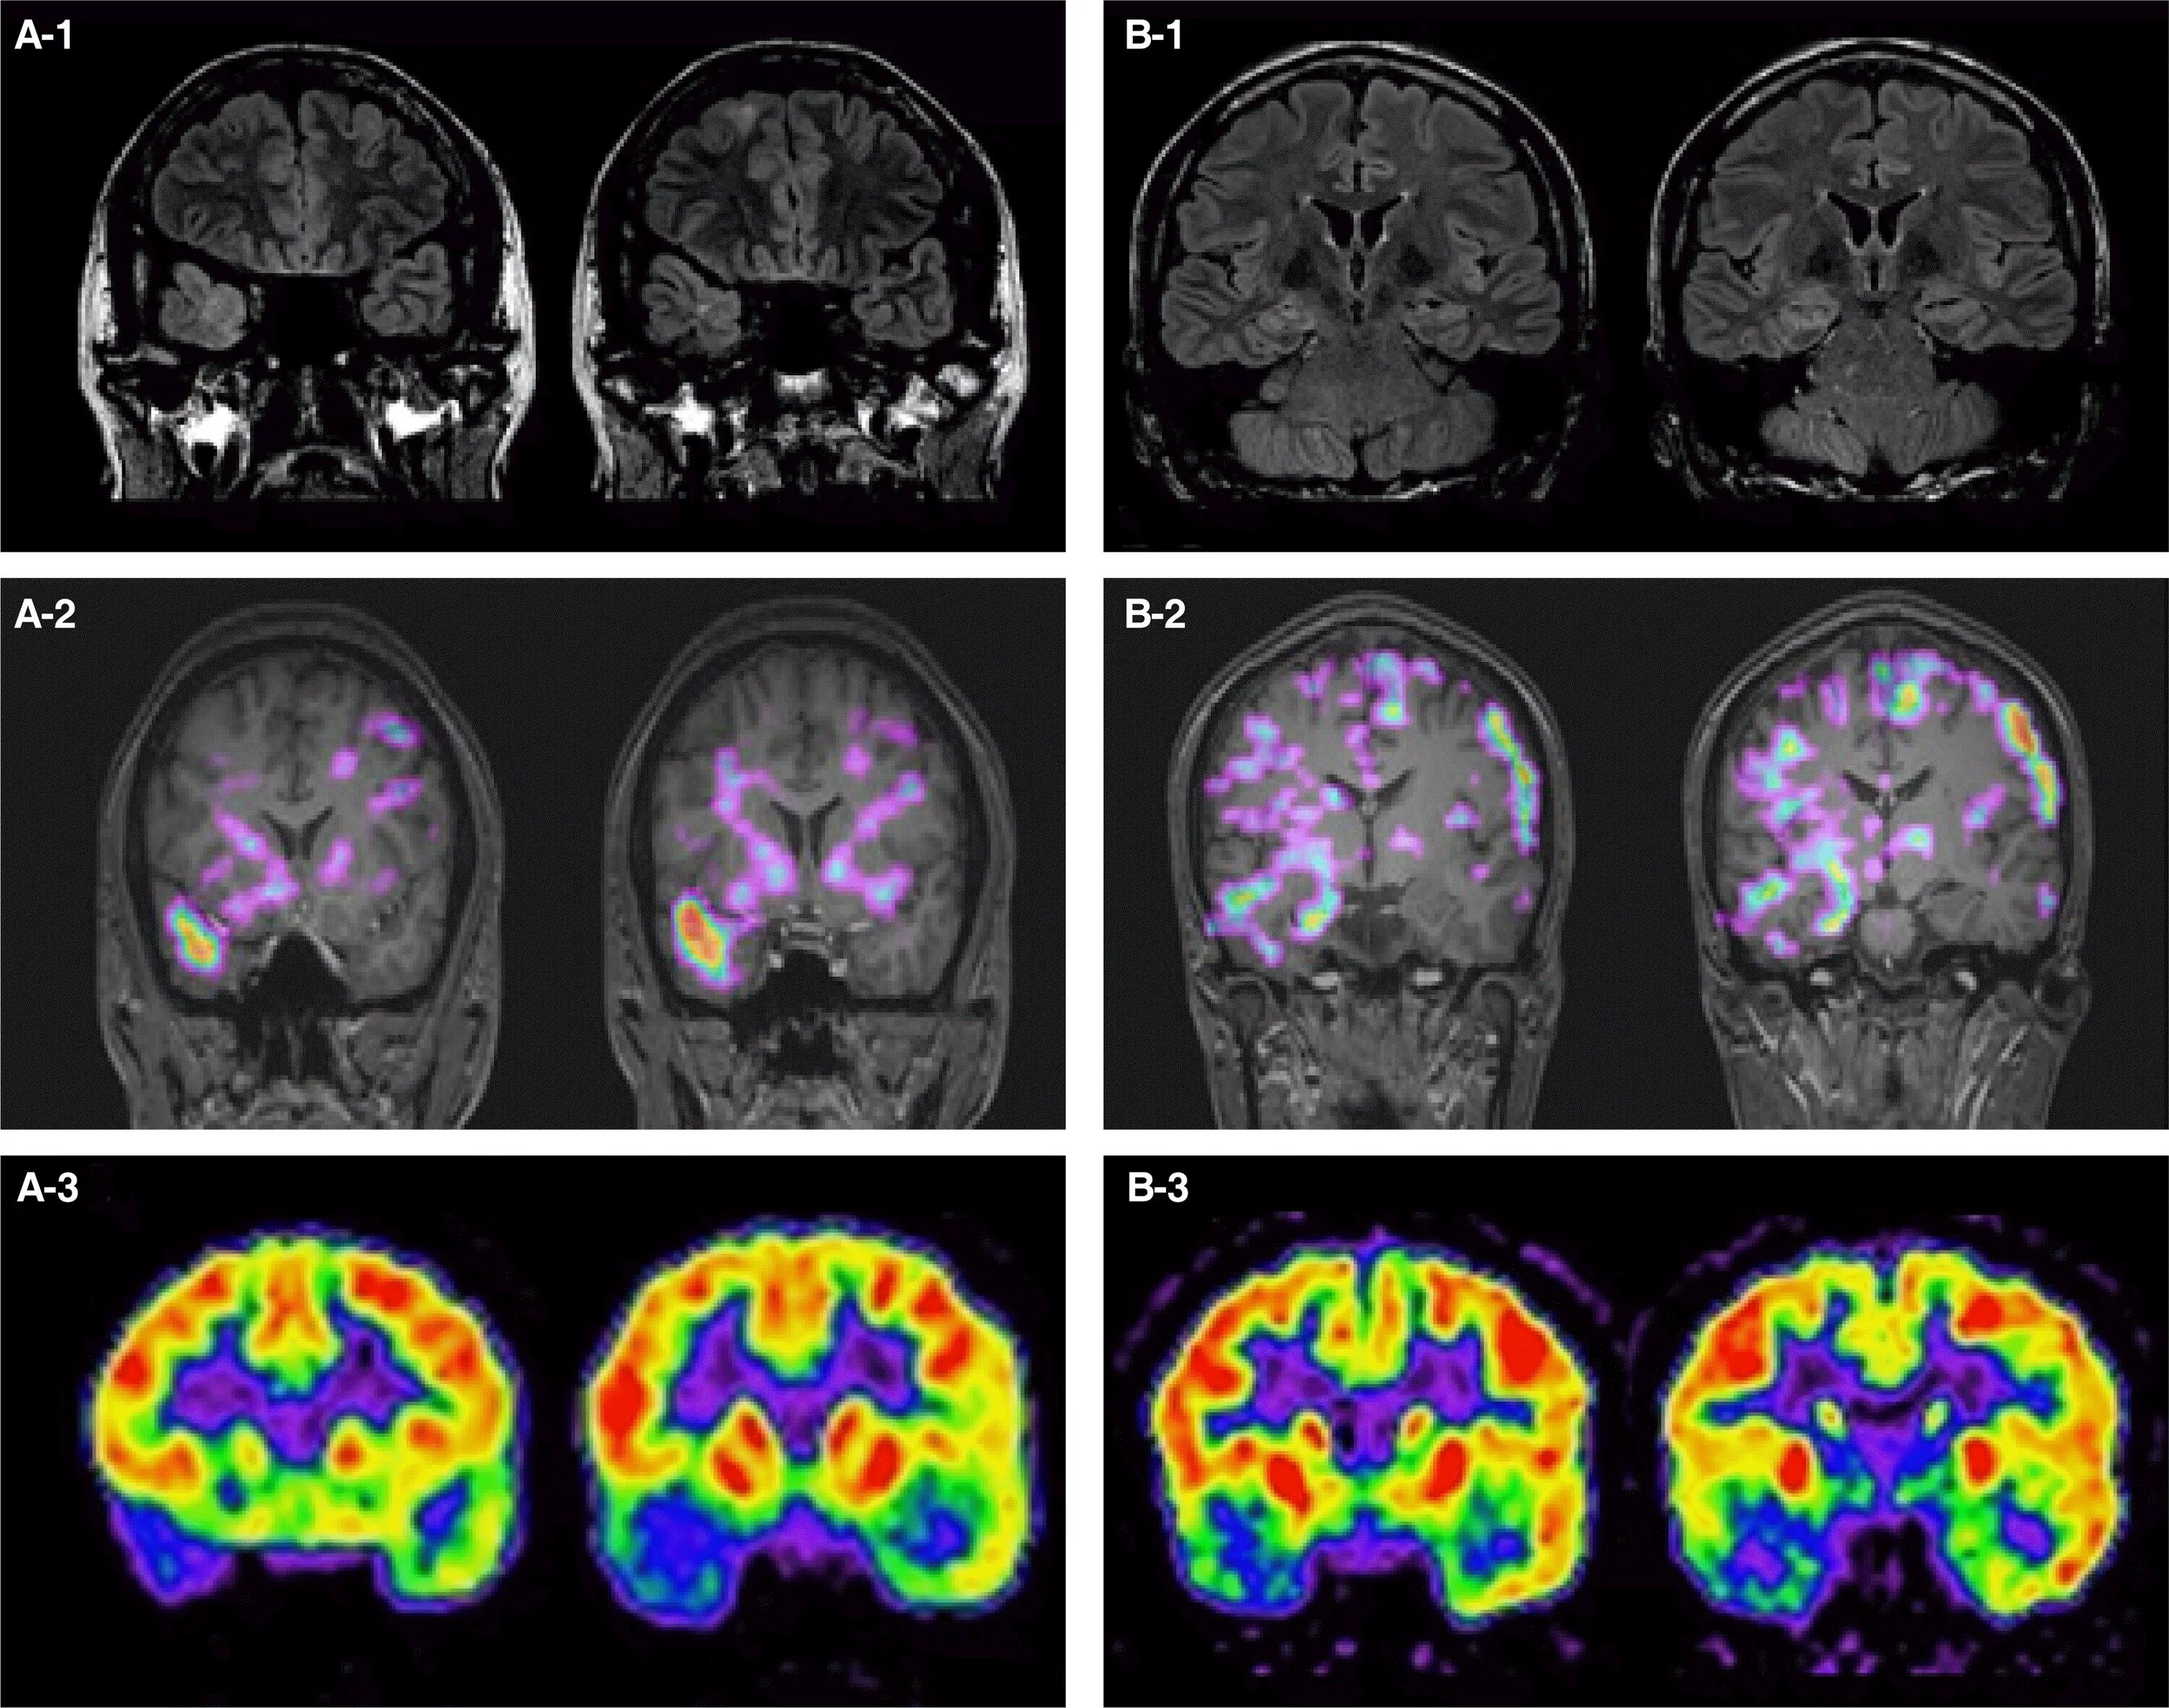

Диффузной биполушарной кортикальной атрофии